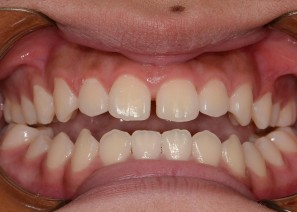

Before

After